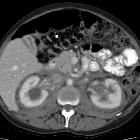

- kidneys and retroperitoneum

- often involved

- usually asymptomatic

- hairy kidney sign: irregular symmetric infiltration of the bilateral perirenal and posterior pararenal spaces

- coated aorta sign: periaortic soft tissue

- inferior vena cava and pelvic ureters are typically spared, which are useful cross-sectional imaging findings for differentiation of retroperitoneal Erdheim-Chester disease from retroperitoneal fibrosis